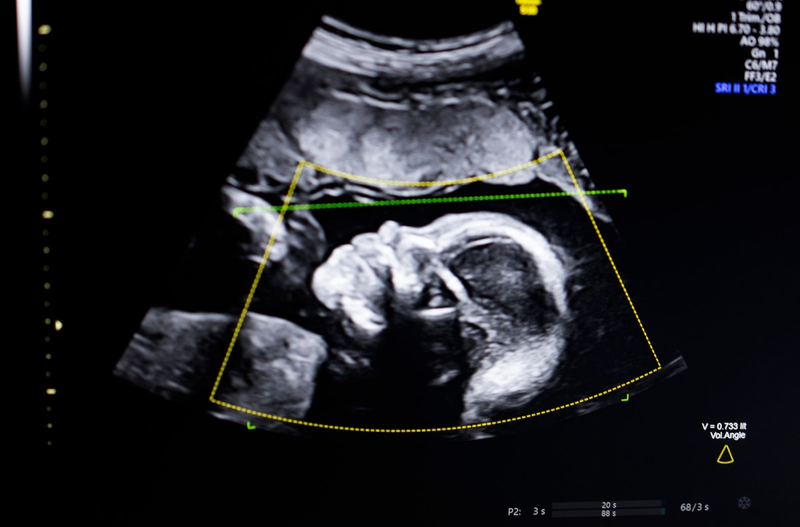

Biotics AI, Battlefield 2023, gains FDA approval for its AI-powered fetal ultrasound product

TechCrunch Disrupt Battlefield 2023 winner, Biotics AI, announced on Monday that it has received FDA clearance for its AI software that helps detect fetal abnormalities in ultrasound images.